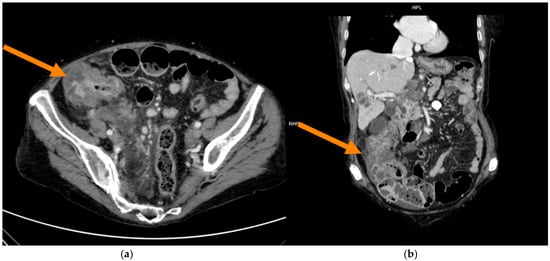

Prediction of Microsatellite Instability in Colorectal Cancer Using Two Internally Validated Radiomic Models

by Antonio Galluzzo, Ginevra Danti, Linda Calistri, Diletta Cozzi, Daniele Lavacchi, Daniele Rossini, Lorenzo Antonuzzo, Sebastiano Paolucci, Francesca Castiglione, Luca Messerini, Fabio Cianchi and Vittorio Miele

Objectives: To develop two different radiomic models based on preoperative contrast-enhanced computed tomography (PP CT) to predict microsatellite instability (MSI) in patients with colorectal cancer (CRC) before surgery. Methods: PP CT scans of 115 CC patients were segmented using 3DSlicer (v5.6.1). Model I [...] Read more.

Objectives: To develop two different radiomic models based on preoperative contrast-enhanced computed tomography (PP CT) to predict microsatellite instability (MSI) in patients with colorectal cancer (CRC) before surgery. Methods: PP CT scans of 115 CC patients were segmented using 3DSlicer (v5.6.1). Model I included images from three different scanners (GE, Siemens, Philips), while Model II used only one scanner (GE). For Model I, 80 patients were used for training and 35 for internal validation; for Model II, 46 and 24 patients were used, respectively. Data on sex, age, tumour location, and MSI genomic status were collected. A total of 107 radiomic features (RFs) were extracted, and 30 and 35 RFs were identified as relevant for Models I and II, respectively, using the t-test or Mann–Whitney test (p < 0.05). The most robust RFs were selected using the LASSO regression method. Both models were internally validated. Results: Model I, based on 2 RFs and 1 clinical feature (LOCATION) achieved an AUC of 0.76 (95% CI: 0.65–0.87) in the training cohort and 0.74 (95% CI: 0.56–0.92) in the validation cohort. Model II, based on 3 RFs, achieved an AUC of 0.85 (95% CI: 0.73–0.96) in the training cohort and 0.72 (95% CI: 0.50–0.94) in the validation cohort. Conclusions: Both radiomic models showed good performance in distinguishing between MSI and non-MSI tumours, potentially reducing the need for invasive histological testing and improving treatment timing. Despite achieving a higher AUC, Model II showed signs of overfitting when compared to Model I, which incorporated two RFs and one clinical feature (LOCATION). Radiomics may function as a non-invasive preoperative screening tool to inform decisions regarding MSI testing and treatment. Building radiomic models on larger, more diverse datasets is preferable to enhance generalizability and reduce overfitting. Full article

(This article belongs to the Section Abdominal Imaging)